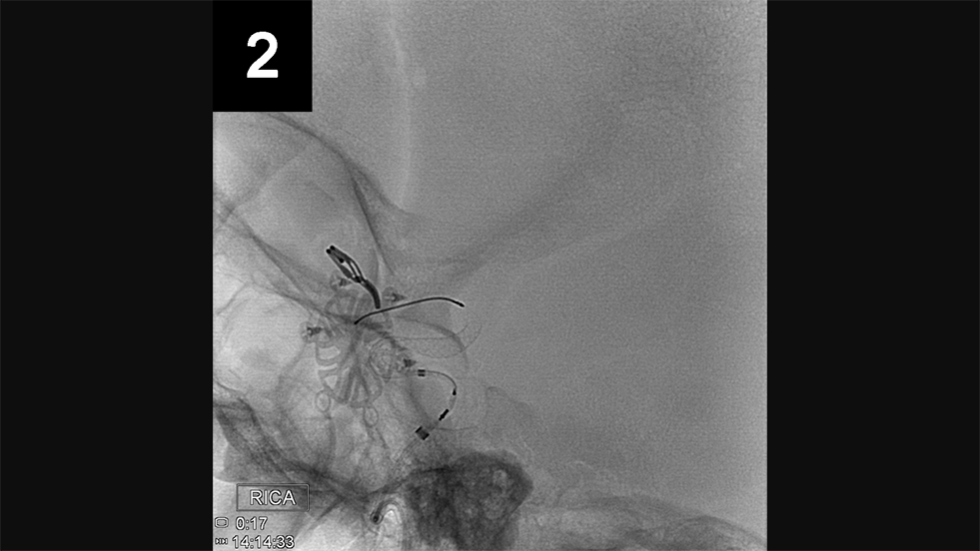

Endovascular Repair

Endovascular (from within the blood vessel) surgery, is performed through a catheter (a hollow, flexible tube) delivered from the groin or leg to the blood vessels in the brain. Thin platinum wires are pushed into the aneurysm, where they conform to the wall of the aneurysm forming a coil mass. Since blood clots form around the coils, the chances of a rupture are greatly reduced. Recovery time is typically only one to three days.